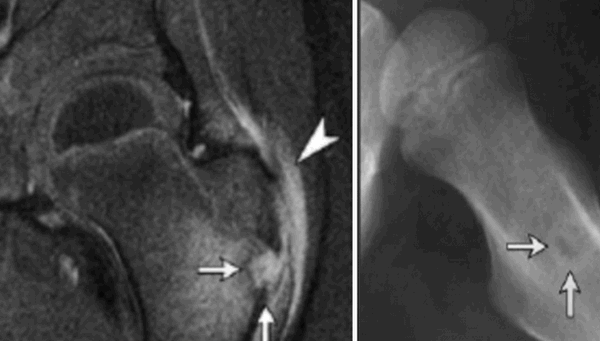

На изображении слева показан расположенный на бедренной головке кэм-остеофит. На изображении справа - рентгеновский снимок после удаления остеофита хирургическим путем.

Подострый остеомиелит на МР-скане и обычной рентгенограмме: отслойка надкостницы (наконечник), гнойный очаг (стрелки)